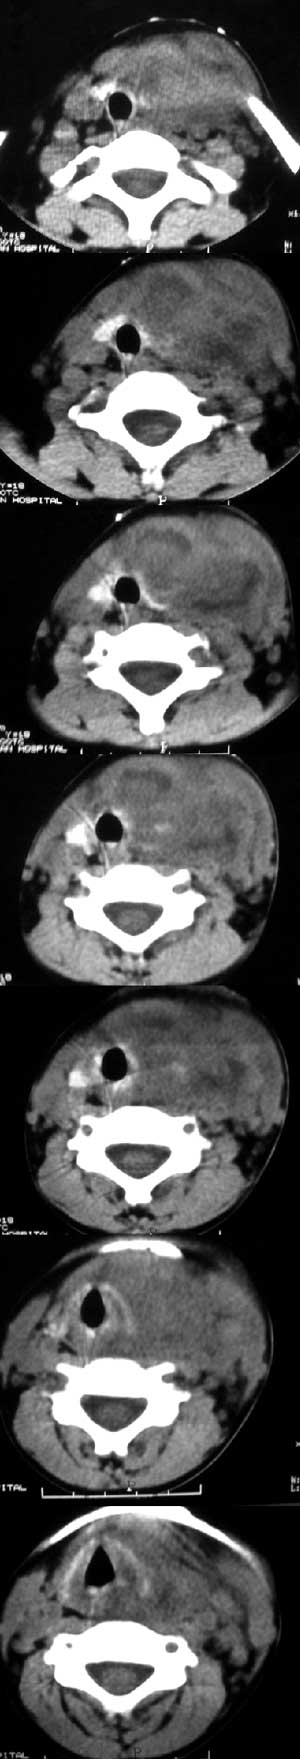

以下是引用jiajie在2007-8-10 11:14:00的发言:[br]左侧颈部锁骨上区巨大软组织密度肿块,左侧甲状腺受侵,边缘不整、界限不清,肿块密度不均,气管受压右移。临床有发热、疼痛病史,考虑急性化脓性甲状腺炎。[br]鉴别诊断,颈部横纹肌肉瘤,男性稍多,2~6岁为发病高峰期,不规则软组织肿块,边界多较清。

以下是引用汪涛同志在2007-8-10 2:10:00的发言:[br]左侧甲状腺巨大软组织病变,虽然临床表现倾向于感染,但皮下脂肪过于清晰,穿刺又未见脓液,应警惕甲状腺恶性病变,结合患儿年龄,考虑为肉瘤可能。